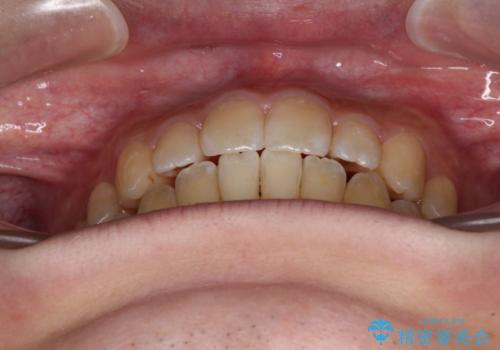

オープンバイトと目立つ銀歯 インビザライン矯正とセラミック修復治療

銀歯のセラミック治療が1番の希望であったため、ここまで歯列がきれいに整うとは思ってなかったようで、大変喜んでいただけました。

銀歯については、矯正治療により咬合関係を改善し、矯正治療後半に修復治療を行うこととしました。

修復治療後に細かい部分をインビザラインで再度仕上げるプランとしました。